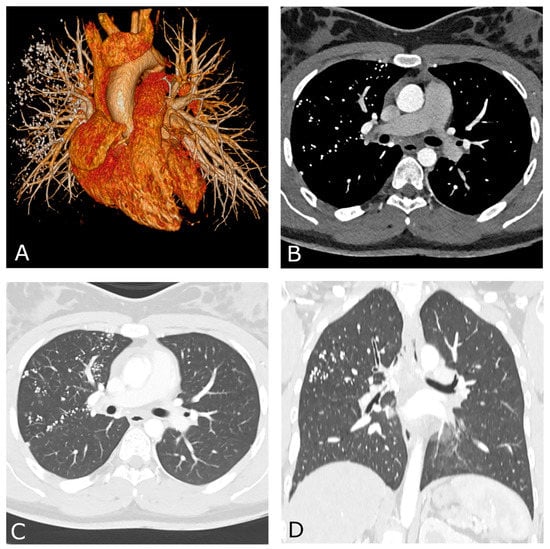

2. Case Report